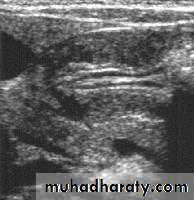

Pyloric stenosis is relatively common and has a male predilection (M:F ~ 4:1), and is more commonly seen in Caucasians 4. It typically occurs between the 4-8 weeks of life. There may be a positive family history. Incidence of hypertrophic pyloric stenosis is approximately 2-5 per 1,000 births per year in most white populations,Hypertrophic pyloric stenosis refers to idiopathic thickening of gastric pyloric musculature which then results in progressive gastric outlet obstruction

In a normal situation, the pyloric muscle thickness (diameter of a single muscular wall on a transverse image) should normally be less than 3 mm (most accurate 3) and the length (longitudinal measurement) should not exceed 15 mm.